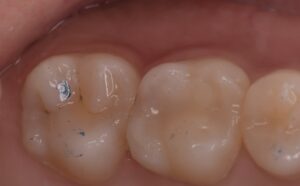

他院で治療をしてもらったが、痛みがずっと続く、ということで当院に来られました。診査の結果、右上6番目の歯の神経が細菌感染を起こしているため、痛みが続いているとわかりました。そこで、2回に分けて、根管治療と修復処置を行いました。

横の右上5番目の歯は神経近くまで虫歯は進んでいましたが、神経を保存することが出来ました。

このまま少なくとも1年以上は経過をみて、問題がないかを確認する必要がありますが、現状は痛みもなく噛めているとのことで治療は無事に終了となりました。